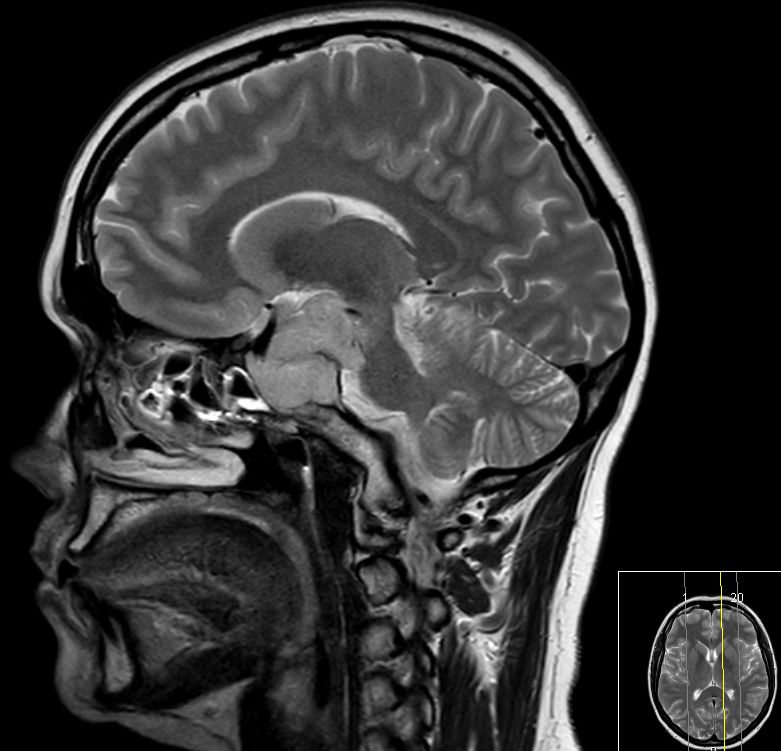

![]() 78jährige Frau. Hypophysenadenom seit 2 Jahren bekannt. Jetzt Deviation des rechten Auges und Kopfschmerzen. | ||||

![]() Das Adenom ist in die Keilbeinhöhle eingewachsen. | |||||

Infraselläre

Ausbreitung mit Ummauerung der Arteria carotis interna rechts. | |||||